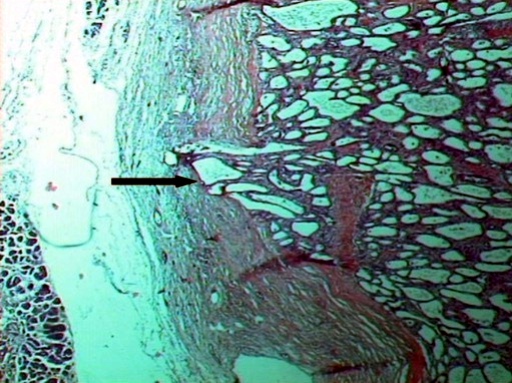

Surgical exploration was performed through a bilateral subcostal incision. A large solid mass on the superior pole of the right kidney and another smaller similar lesion on the inferior pole were confirmed. The pancreatic parenchyma was multilobular and of woody texture, indicative of chronic pancreatitis. A large hard mass in the pancreatic head was severely compressing the second part of the duodenum close to the ampulla, without invasion of the surrounding organs. After intraoperative evaluation of these findings, we proceeded with an en-bloc total pancreaticoduodenectomy and splenectomy, followed by a radical right nephrectomy. The patient had an uneventful postoperative course and was discharged on the 7th postoperative day. Histological examination showed two well-differentiated clear cell renal adenocarcinomas in the upper and lower poles of the right kidney. The pancreas measured 15x5x4.5 cm, had a woody texture and contained one hard, microcystic mass measuring 5x5x4 cm in the head, and one multilobulated cystic lesion in the body and tail, measuring 5x2x2 cm. Both lesions proved to be serous microcystic adenomas with cellular and architectural atypia. The adenoma of the pancreatic head harbored a small focus of microscopic infiltration of its fibrous capsule (Figure 3). The rest of the pancreatic parenchyma exhibited severe changes characteristic of chronic pancreatitis, as the result of significant compression of the pancreatic duct by the two large serous microcystic adenomas.

Figure 3. Section of the serous microcystic adenoma in the pancreatic head (H&E, x25). Note the infiltration of its outer fibrous capsule from the parenchyma within. |